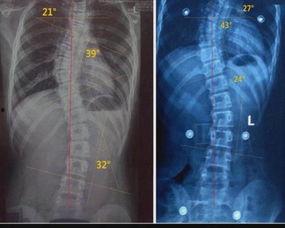

脊柱侧弯,顾名思义,就是脊柱在X光片上呈现侧弯的形态。这种疾病在成年人中并不少见,据统计,我国成年人脊柱侧弯的发病率约为2%-3%。脊柱侧弯不仅会影响外观,还会导致腰背疼痛、活动受限等问题。